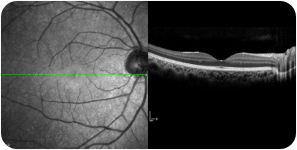

정상안

당뇨망막병증으로 인한 황반부종

중심성장액맥락망막병증